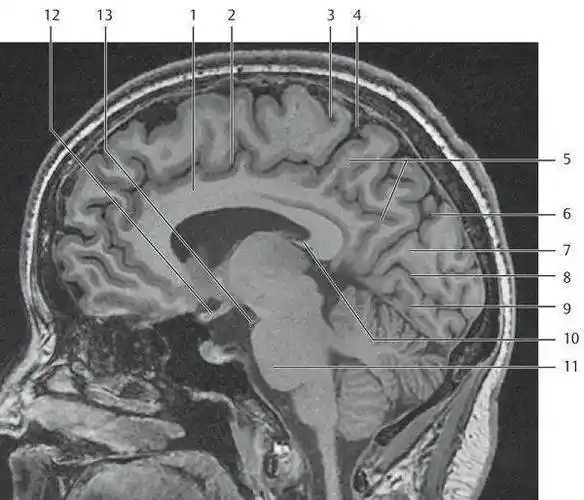

超赞!颅脑大体及磁共振断层解剖(轴位)

高清颅脑mri最全轴位影像解剖人手一册

312.头部磁共振影像解剖

脑mri必备丨最详细的脑mri解剖

mri颅脑横断面解剖图谱

这个高清颅脑断层解剖图谱实在太棒了!【磁共振 大体标本】